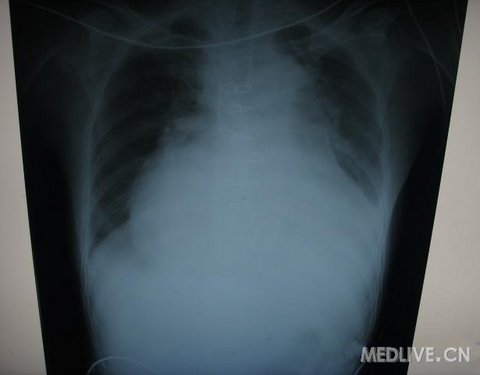

胸片表现

http://webres.medlive.cn/upload/000/060/740